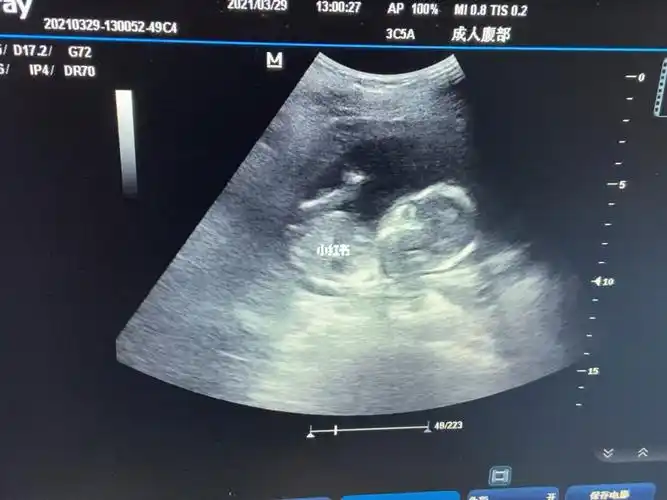

翻到了四个月时候宝宝在妈妈肚子里的样子